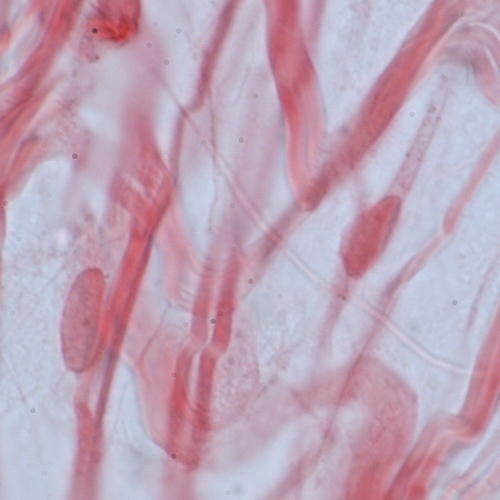

• Tendons and ligaments consist primarily of type I collagen fibrils and small amounts of other components that help organize the type I fibrils into fibres and fibre bundles.

Differences among the connective tissues also depend on the three-dimensional organization of the molecular components. The type I collagen fibrils in tendon are packed into thick, parallel bundles of fibres, whereas type I collagen fibrils in skin are randomly oriented. In cortical bone, helical arrays of type I collagen fibrils are deposited around haversian canals.